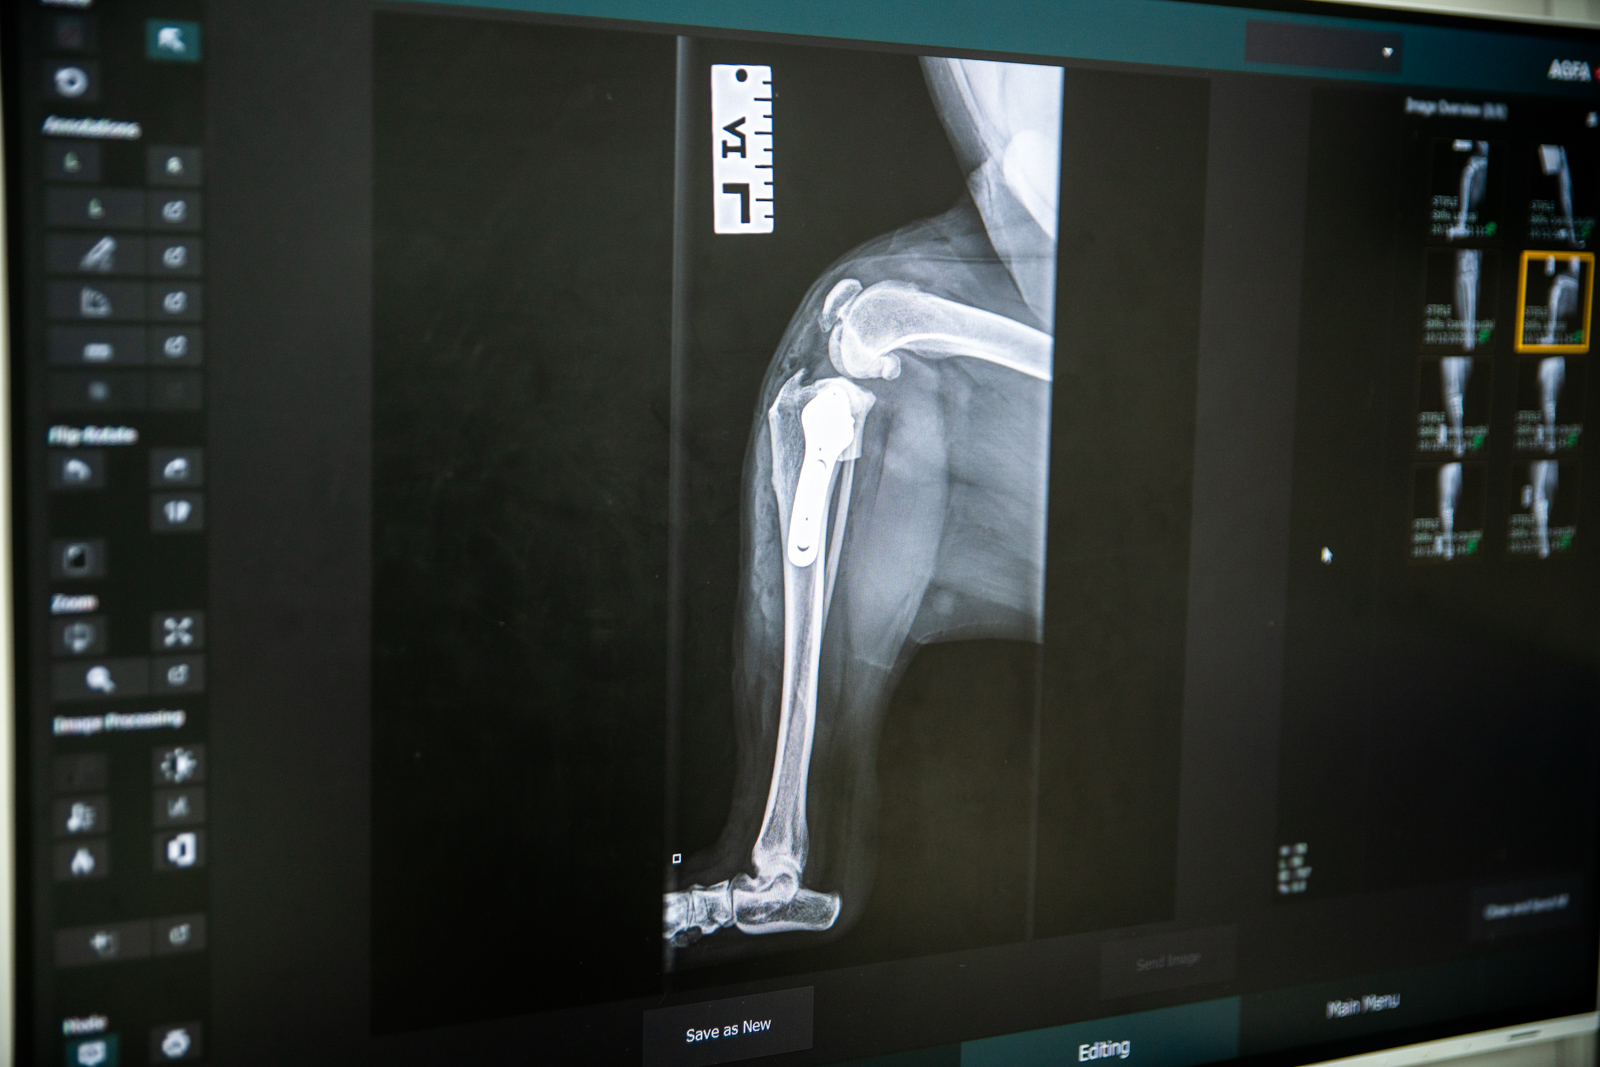

Pet Owner Case Studies Read our Client Case Studies below. Ellie, severe hip arthritis Chloe, elbow dysplasia Juno, cruciate ligaments Lexi, Humeral Intercondylar Fissure Ellie, severe hip arthritis Chloe, elbow dysplasia Juno, cruciate ligaments Lexi, Humeral Intercondylar Fissure